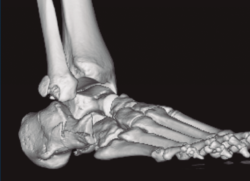

Se trata de un varón de 19 años que ingresa en reanimación tras precipitarse desde una altura de aproximadamente 10 metros. El paciente presenta una fractura estallido de L3 con afectación del canal medular junto con una fractura del vértice inferior de L4, así como una fractura luxación de calcáneo, asociada a una fractura del maléolo peroneo y del maléolo tibial posterior (Figuras 1 a 6) diagnosticadas mediante TC total body (por eso no se dispone de radiografías simples al momento del ingreso). Como podemos comprobar, se trata de una fractura de doble trazo de tipo hundimiento/depresión de la carilla articular (Figuras 5 y 6).

Figura 5. Fractura maléolo peroneo, luxación astrágalo, fractura de doble trazo en calcáneo.

Figura 6. Fractura de doble trazo; se evidencia afectación de la articulación calcaneocuboidea.